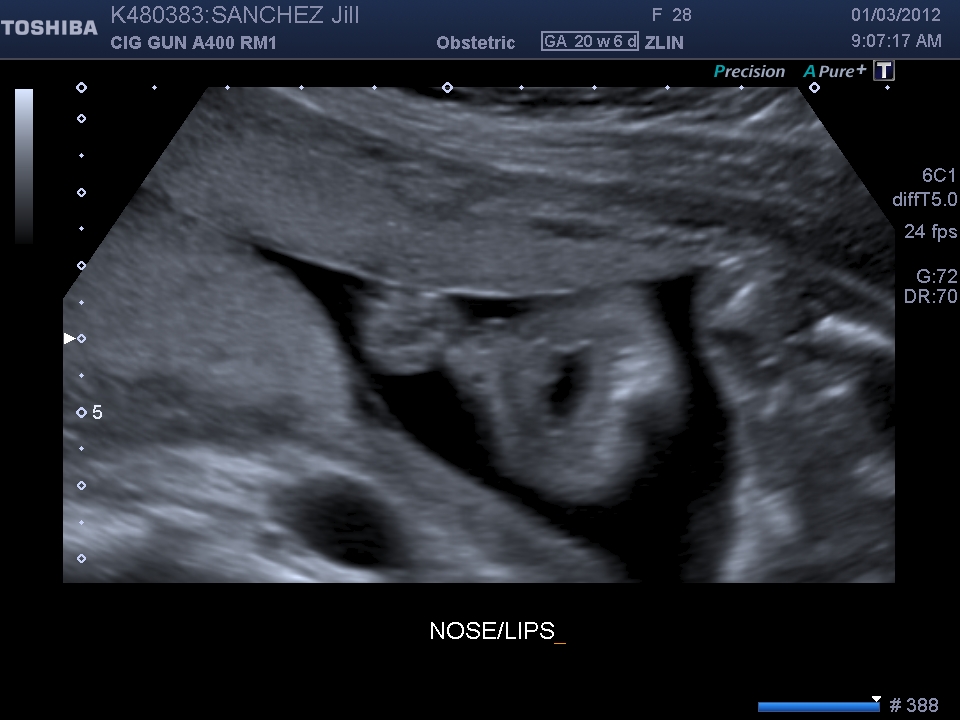

Here he's playing peek-a-boo! Cute little lips and nose! While we were looking at his head/face, he kept making an "o" shape out of his lips. It was just too cute!